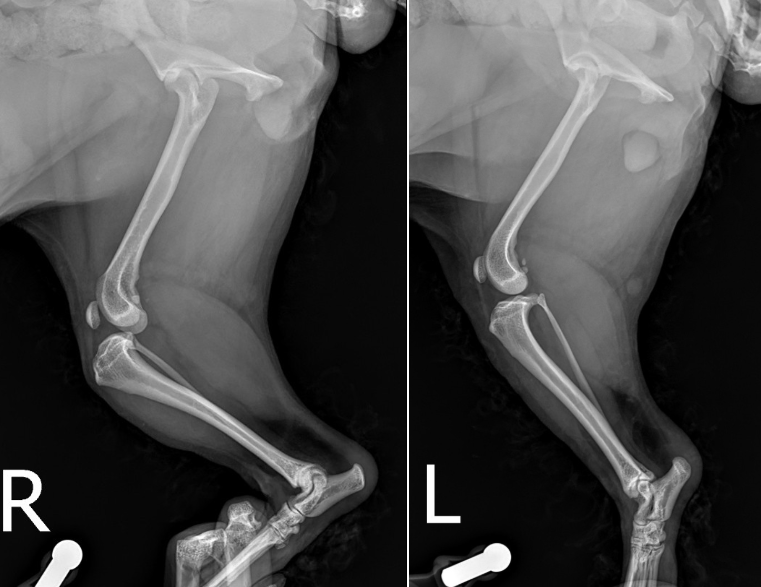

TPLO 수술을 계획하기 위해서는 엑스레이 촬영 했을 때 좌측에 보이는 calibration ball 을 같이 포함하여 촬영을 해야합니다. ▼

그리하여 명란이는 우측 십자인대 단열에 대한 TPLO 수술을 계획하게 되었습니다. TPLO 는 무릎의 각도롤 교정해서 십자인대가 밀리면서 유발되는 통증을 느끼지 못하도록 하는 수술법입니다.

저희 병원은 vpop PRO 프로그램을 사용해서 환자 개개인에 맞는 수술을 계획 할 수 있습니다.

프로그램을 통해 각도를 얼마나 돌릴 지, 어떠한 플레이트와 스크류를 사용하여 고정을 할지 ,수술 후 예상되는 변화는 어떤지 미리 볼 수 있기 때문에 충분한 계획을 가지고 수술을 진행하게 됩니다. ▼